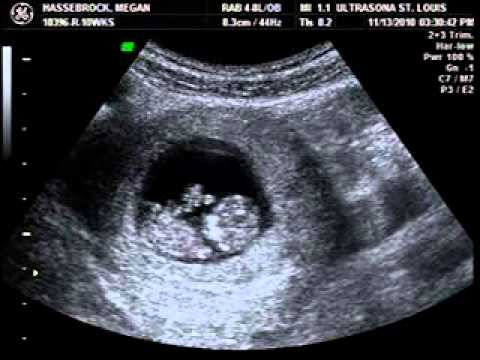

Baby Jumping Around At 10 Week Ultrasound

She was able to get somewhat of a measurement though. Hello All I just went for my third ultrasound. Baby is measuring right on schedule at 10 weeks 6 days 411cm and the heart rate is 164.

The neck fold looks normal so all signs are pointing to a healthy and well developing baby. In this video posted on YouTube you can see this baby jump and move around in its mothers.